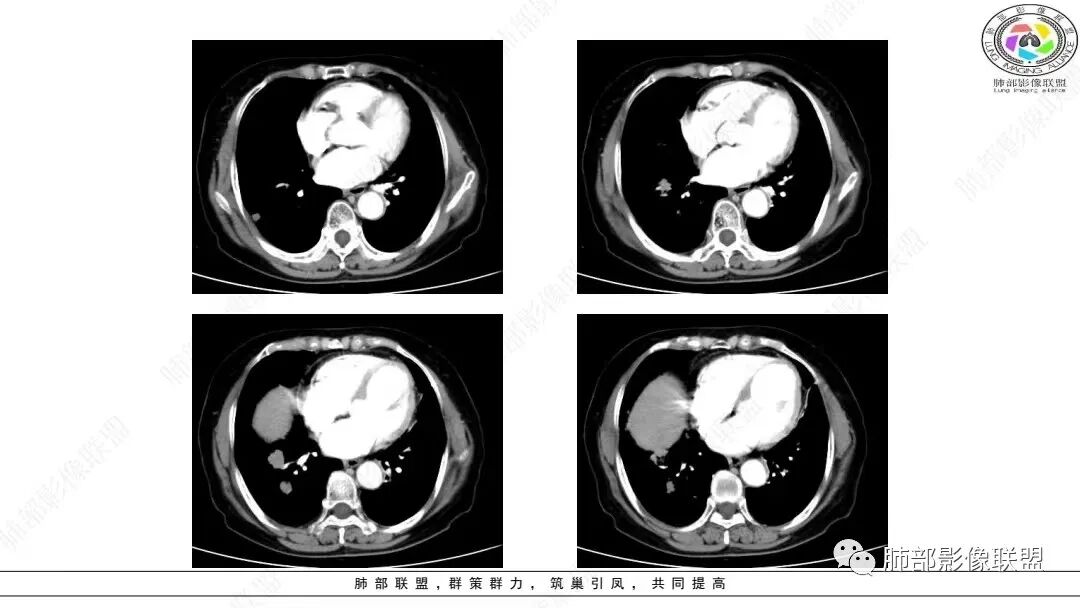

2.影像学特点:右肺上叶前段胸膜下不规则较大团块影,边界清楚欠光整,浅分叶,肺血管支气管出入,边缘膨隆胸膜凹陷具有一定张力,未见典型粗短毛刺,部分围以边界清楚的磨玻璃影,灶周小叶间隔增厚。块影密度不均,渐进性强化,可见砂砾样钙化,未见明显液化坏死或空洞。增强后病灶显示渐进性强化。MIP显示病灶内肺动脉穿行、并部分肺动脉受侵变细。纵隔及右锁骨上(胸廓入口)见肿大淋巴结。两肺可见多发大小不一的结节影,边界清楚,随机分布。

病灶较大较光整,支气管出入,缀以边界清楚磨玻璃影,有一定张力,不均匀强化,疑及肺腺癌或者大细胞肺癌都在情理之中。双肺多发病灶,符合转移瘤特征。     注意胸椎体溶骨性吸收破坏,突破骨皮质,经验上这样的改变更支持转移而不支持淋巴类肿瘤。

本组大部分病灶(64.75%)CT平扫密度均匀;增强后多数病灶以中度(71.75%)、渐进性强化(75.13%)为主,动脉期病灶内常见异常细小杂乱血管影(55.96%)。    笔者据此认为密度均匀且不易出现坏死、呈中度渐进性延时强化为肺LELC的特点,可能与病灶内部含有丰富的淋巴细胞浸润和大量纤维组织增生及胶质有关;病灶内部分细小杂乱血管影可追踪为支气管动脉,推测可能为新生肿瘤血管,提示肿瘤血供丰富,不易出现坏死;但新生肿瘤血管通常不成熟,血管通透性增高,致使对比剂外渗,使肿瘤表现为延迟强化。肺LELC生长较快时,由于血供不足,也可出现液化坏死及钙化等改变。肺LELC密度均匀、液化坏死较少及延迟强化,可作为其与肺鳞癌或腺癌的鉴别要点。

多数学者认为血管支气管包埋征是肺LELC的特征性表现。本组41.97 0A(81/193)病灶内部动脉期见血管包埋征,而血管形态正常,无明显受侵、狭窄,与上述研究报道相符,可能提示肺LELC具有类似淋巴瘤相似的特点,即易浸润周围结构,引起间质增厚、肺泡壁破坏及肺泡腔充盈,但较少侵犯血管[1 3|。但本组108例(108/193,55.96%)表现为血管受侵、狭窄,75.82%支气管受累狭窄闭塞,可能提示肺LELC病灶内血管受侵狭窄及支气管破坏较淋巴瘤更多见[1 3|,较大肺LELC病灶更易出现血管、支气管受侵、破坏。